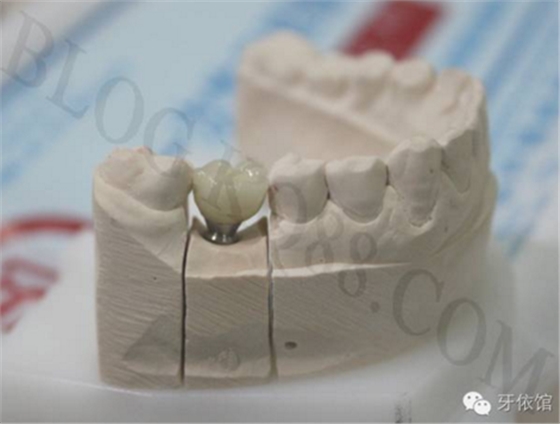

烤瓷牙制作完成。

將基臺定位器安裝在模型上的粘結(jié)基臺上,用螺絲刀旋下中央螺絲。

將基臺定位器和基臺同時(shí)在口內(nèi)就位,用手旋緊中央螺絲,試戴烤瓷牙,調(diào)整咬合,再用扭矩扳手旋緊中央螺絲。